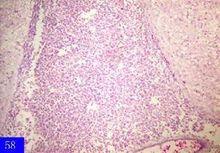

腦膜炎球菌屬奈瑟氏菌屬,為革蘭陰性球菌,呈卵圓形,常成對排列。該菌僅存在於人體,可從帶菌者鼻咽部,病人的血液、腦脊液和皮膚瘀點中檢出。腦脊液中的細菌多見於中性粒細胞內,僅少數在細胞外。普通培養基上不易生長,在含有血液、血清、滲出液及卵黃液培養基上生長良好,一般於5%~10%的二氧化碳環境下生長更好。本菌對寒冷、乾燥及消毒劑極為敏感。在體外極易死亡,病菌能形成自身溶解酶,故採集標本後必須立即送檢接種。病原菌自鼻咽部侵入人體,如人體免疫力強,則可迅速將病原菌殺滅,或成為帶菌狀態;若體內缺乏特異性殺菌抗體,或細菌毒力較強時,則病菌可從鼻咽部黏膜進入血液,發展為敗血症,繼而累及腦脊髓膜,形成化膿性腦脊髓腦炎。在敗血症期,細菌常侵襲皮膚血管內壁引起栓塞、壞死、出血及細胞浸潤,從而出現瘀點或瘀斑。由於血栓形成,血小板減少或內毒素作用,內臟有不同程度的出血。

暴髮型敗血症是一種特殊類型,過去稱為華-佛氏綜合徵,曾認為是由於雙側腎上腺皮質出血和壞死,引起急性腎上腺皮質功能衰竭所致。現已證明腎上腺皮質功能多數並未衰竭,在發病機理中並不起主要作用,而由於腦膜炎球菌的脂多糖內毒素可引起微循環障礙和內毒素性休克,繼而導致播散性血管內凝血(DIC)則是其主要病理基礎,暴髮型腦膜腦炎的發生和發展亦和內毒素有關。第Ⅲ型變態反應亦可能在發病機理中起某些作用,如在受損的血管壁內可以見到免疫球蛋白、補體及腦膜炎球菌抗原的沉積。